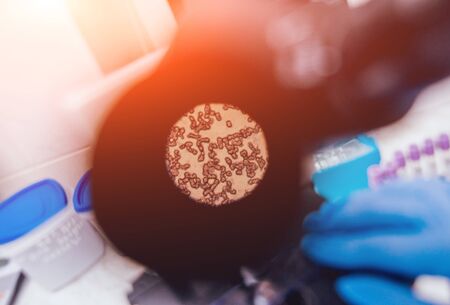

gram stian was show gram positive bacilli.

Dense Clumps of Rod-Shaped Bacteria (Bacilli) Under a Microscope